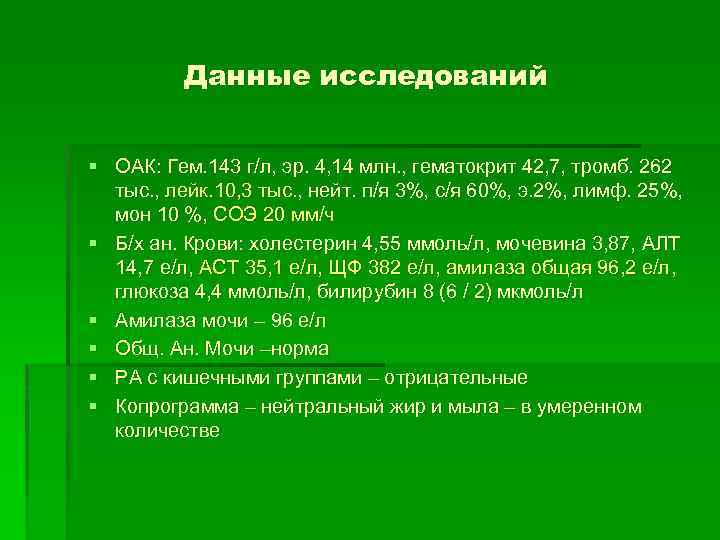

Данные исследований § ОАК: Гем. 143 г/л, эр. 4, 14 млн. , гематокрит 42, 7, тромб. 262 тыс. , лейк. 10, 3 тыс. , нейт. п/я 3%, с/я 60%, э. 2%, лимф. 25%, мон 10 %, СОЭ 20 мм/ч § Б/х ан. Крови: холестерин 4, 55 ммоль/л, мочевина 3, 87, АЛТ 14, 7 е/л, АСТ 35, 1 е/л, ЩФ 382 е/л, амилаза общая 96, 2 е/л, глюкоза 4, 4 ммоль/л, билирубин 8 (6 / 2) мкмоль/л § Амилаза мочи – 96 е/л § Общ. Ан. Мочи –норма § РА с кишечными группами – отрицательные § Копрограмма – нейтральный жир и мыла – в умеренном количестве